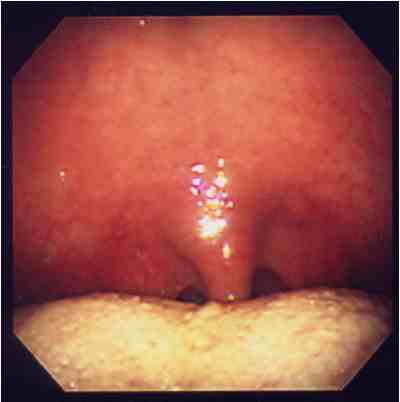

閉塞型睡眠時無呼吸症候群(OSAS)の閉塞部位はどこ?

また,原因となる疾患にはどんなものがあるの?

(OSASは気道の閉塞が原因ですから、気道を狭くする疾患が隠されています。) 睡眠時無呼吸症候群の診断はどうやってするの?